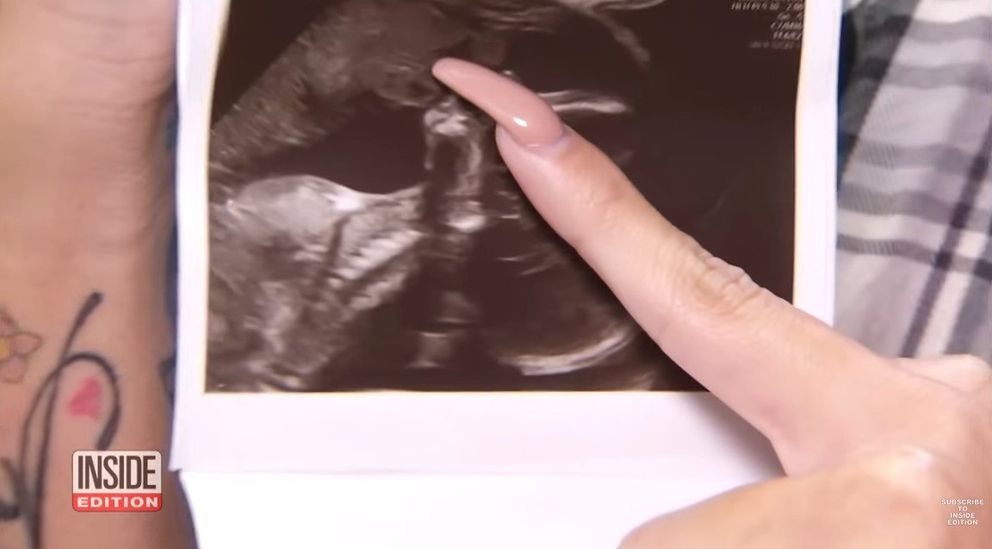

Carrillo izgatottan várta a 20 hetes ultrahangot, de a magzat nem volt hajlandó megjelenni, amikor eljött az idő. A baba vonaglott, és a radiológusnak szinte lehetetlen volt felvételt készíteni az arcáról.

Végül a gép rögzítette a magzat oldalprofilját, és a pár elindult, hogy a jó hírt: a baba fejlődését és csettintését megossza a családdal és a barátokkal.

Mikor a pár az ultrahangra pillantott, először semmi szokatlant nem vettek észre. Miután azonban az ultrahangfotót megosztották a Facebookon, sok kommentelő rámutatott valami különlegesre.

Először egy nő azt írta, hogy egy angyal csókolgatja a babát. Emiatt Carrillo közelebbről is megnézte a képet. Egyetértett a kommentelővel, sőt, értelmet is adott az egésznek.

Carrillo szerint a gyermekéhez közel hajoló angyal az édesapja! A várandós anyuka később egy hírportálnak elmondta, hogy az apuka lehajolt, hogy megcsókolja unokáját.

Az anyuka véleményekre volt kíváncsi, és elküldte a képet a legközelebbi rokonainak, és hozzá hasonlóan ők is élénken látták az apukáját. Shantel szerint az ultrahang pont olyan, mint egy kép, amit édesapjáról készítettek az első gyermekével, Pacheco-val.

A képen az apa egy piros sapkát viselt ahogy a csecsemőre nézett. Carrillo kiemelte az egyedi arcát és orrát is, amit az ultrahangos képen is észre vett.